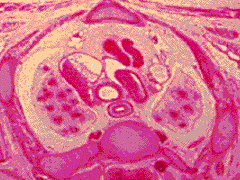

C7:

Sternum. Thymus gland. L brachiocephalic vein.

Brachiocephalic trunk. Trachea.

Oesphagus. Apex of R lung in pleural cavity